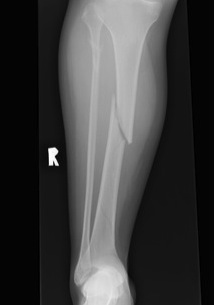

Tibial Stress Fractures

EpidemiologyTibial Stress Fracture

Athletic / high impact exercises

First described in ballet dancers (Burrows 1956)

- tension side of bone / lateral side

- progression to complete fracture has been well documented in athletes